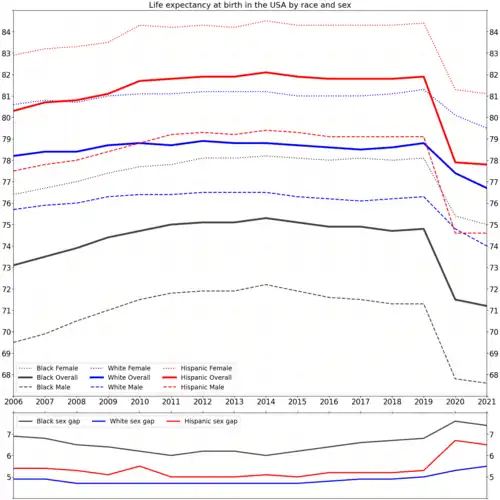

Latinos

In the US, the Latino demographic is most likely to develop metabolic syndrome - the combination of high blood pressure, high blood sugar, elevated triglyceride levels, and abdominal obesity - which not only increases the risk of cardiac events and type 2 diabetes but also is associated with lower neurocognitive function during midlife.[100] This takes place even though life expectancy for Latinos in the US is higher than for white and black.[101][102]